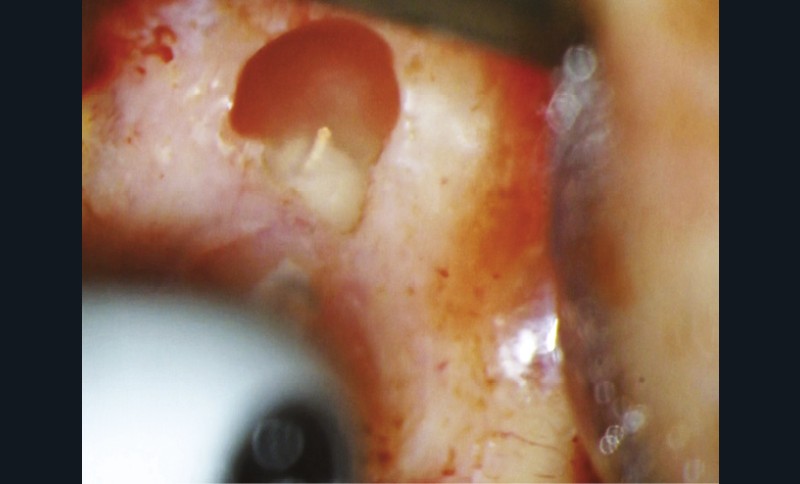

Si l’étude de Peters [18] nous montre que l’instrumentation laisse 35 % du volume canalaire non instrumenté, Ricucci et Siqueira montrent que la préparation physico-chimique n’élimine que partiellement les tissus nécrotiques à l’entrée des canaux latéraux, des isthmes et des ramifications apicales, en laissant des tissus enflammés et infectés, en association avec des lésions apicales [29] (fig. 4 et 5).

Fig. 4 – Coupe d’une racine mésiale de molaire mandibulaire avec deux canaux traités. Coupe à 3 mm de l’apex, coloration Brown et Brenn, technique modifiée par Taylor. Ces images montrent un isthme étroit avec une infection bactérienne, ce qui prouve l’importance de désinfecter et d’inclure l’isthme dans les traitements conventionnels et dans les rétropréparations apicales en chirurgie endodontique.